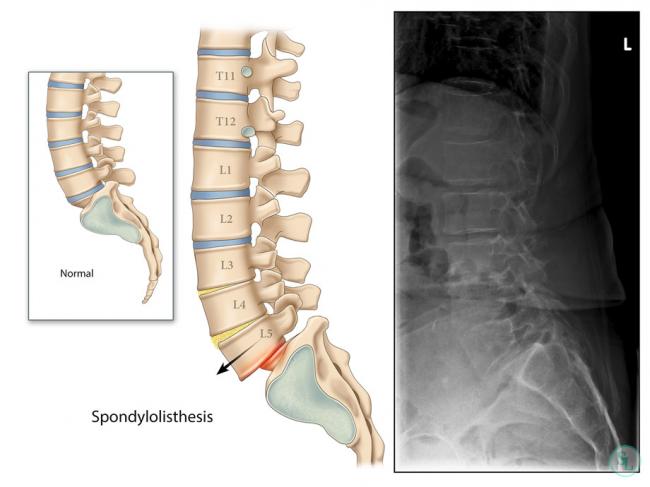

При смещении, один из позвонков сдвигается в сторону, нарушая нормальное функционирование позвоночника. В зависимости от того, в какую сторону сместился позвонок, выделяют три разновидности течения заболевания.

Самым распространенным считается антеспондилолистез, при котором позвонок сдвигается вперед. Сдвиг позвонка назад, получил название ретроспондилолистез, а в какую-либо сторону – латероспондилолистез.

В подавляющем большинстве случаев, смещаются 4 или 5 позвонок, что обусловлено повышенной нагрузкой на эту часть спины. Это очень опасное и болезненное состояние, требующее длительной комплексной терапии. Кроме того, при сдвиге пятого позвонка, обязательно диагностируют растяжение связок, подвывихи, что нередко требует проведения хирургической операции.